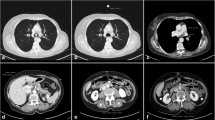

Both types of sequential scans resulted in a lower radiation dose, lower number of acquired slices and longer scan time, as shown in Table 2. Acquisition scan time was ≤33 s in all cases. The sequential scan at 50 mAs resulted in a median effective dose of 0.09, comparable to that of a digital chest X-ray [22]. Figure 2 illustrates axial, coronal and 3D reconstructions of the three acquisition protocols in a representative animal.

Scanning protocols. Axial (upper panels), coronal (middle panels) and 3D reconstructions (lower panels) of the three acquisition protocols in a representative animal. Colors in the 3D reconstruction represent clusters of lung tissue: hyper-aerated (blue), normally aerated (green), poorly aerated (yellow), non-aerated (red)

Figure 3 shows the Bland-Altman comparison for the non-aerated compartment between the experimental protocols and the reference scans in pigs and humans. The Additional file 1 contains extensive details on the analysis results of both human and animal scans.